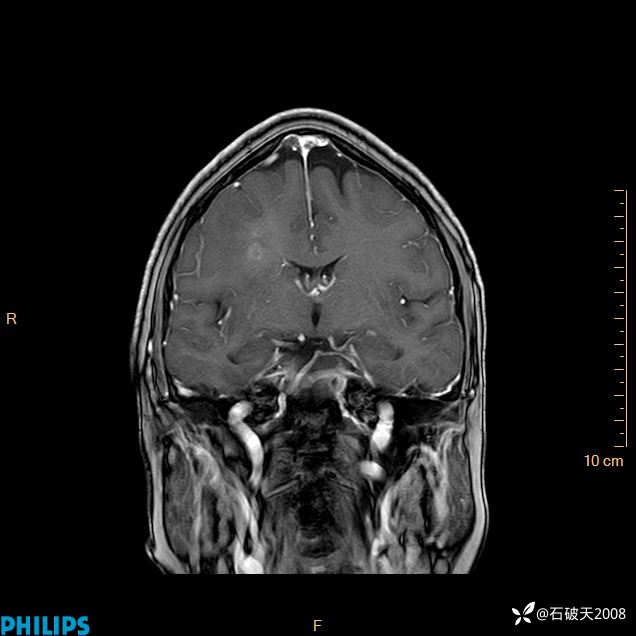

2024.2.21MR

增强冠状位